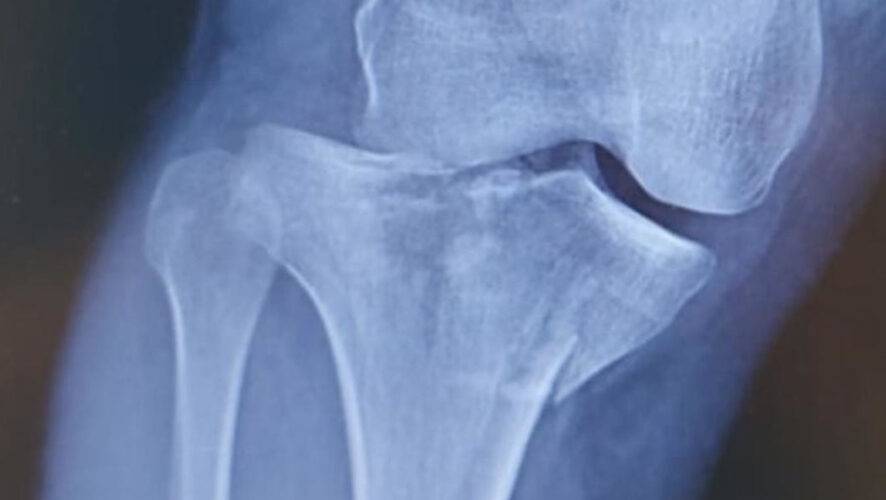

В Казани прооперировали человека, упавшего с самоката — он получил многооскольчатый перелом верхнего суставного конца большеберцовой кости с разрывом боковых связок. Об этом рассказали в телеграм-канале горбольницы №7.